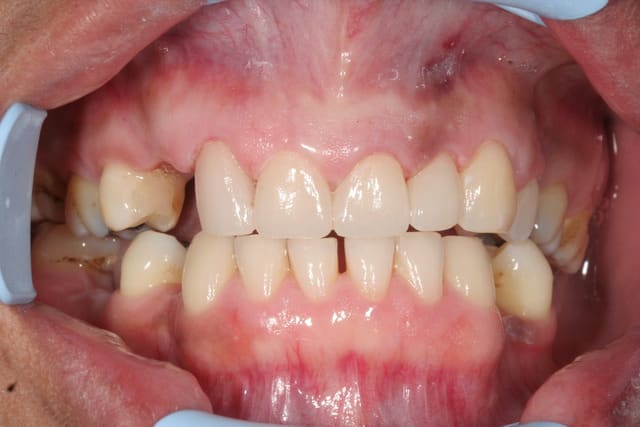

Ou encore fait dans la matinée

Ps: pas de soucis d'occlusion, juste une propulsion pendant la photo finale. Elle avait dû tenter de retrouver machinalement ce contact bout à bout.

Img 6200 bcvdwg - Eugenol

Img 6201 ivt2xu - Eugenol